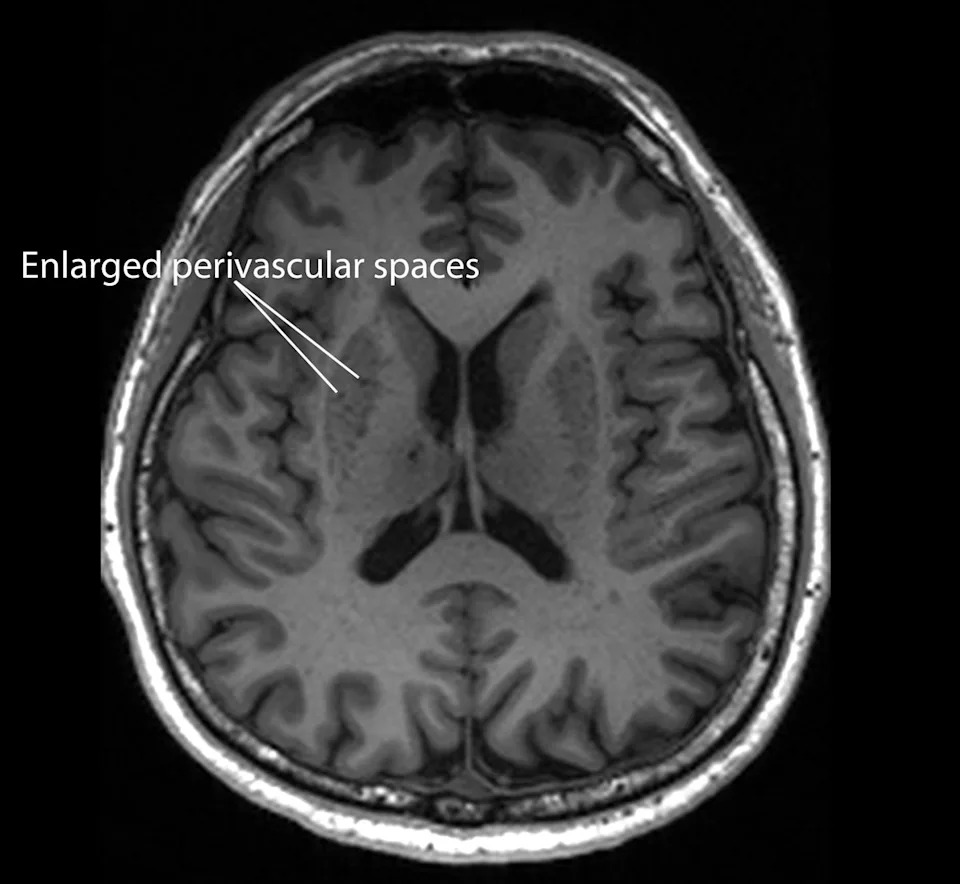

Researchers analyzing nearly 1,000 brain scans from a multi-ethnic Singapore cohort—including about 350 people without cognitive complaints—found that enlarged perivascular spaces (PVS), small channels that help clear waste from the brain, were more common in people with mild cognitive impairment. On standard MRI sequences these widened channels appear as conspicuous fluid-filled spaces.

The team reported that the presence of enlarged PVS correlated with several blood markers associated with Alzheimer’s pathology: four out of seven blood molecule measurements, including measures related to beta-amyloid plaques and tau tangles. The study, published in the journal Neurology, suggests that routine MRI scans could help flag individuals at higher risk of developing Alzheimer’s before major brain damage occurs.